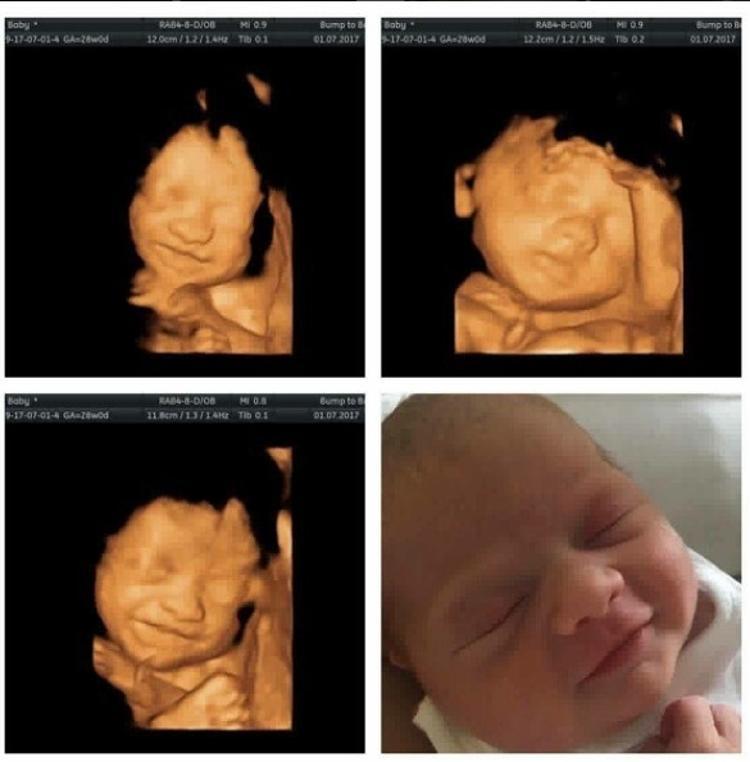

Dogduktan Sonra Ultrasondaki Fotograflari Ile Ayni Pozlari Veren Bebekler